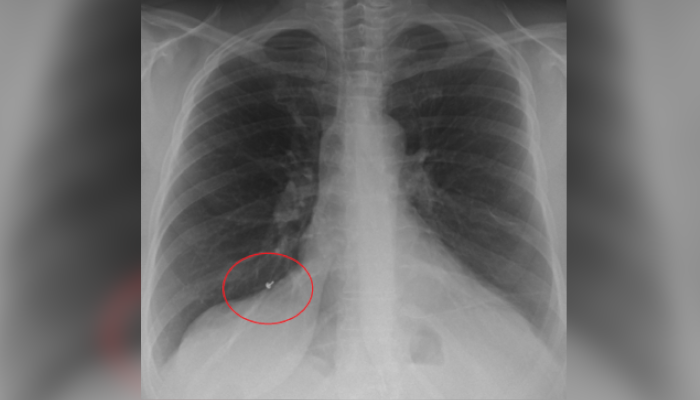

മൂന്ന് സ്ത്രീകളുടെ ശ്വാസകോശത്തില് നിന്നും മൂകുത്തി നിക്കം ചെയ്തു. കൊച്ചിയിൽ കഴിഞ്ഞ രണ്ടാഴ്ചക്കിടെ മൂന്ന് സ്ത്രീകളുടെ ശ്വാസകോശത്തിൽ നിന്നാണ് മൂക്കുത്തിയുടെ ഭാഗങ്ങൾ കണ്ടെടുത്തത്. അമൃത ആശുപത്രിയിലെ ഇന്റർവെൻഷണൽ പൾമനോളജി വിഭാഗത്തിലാണ് മൂന്ന് സ്ത്രീകളുടെ ശ്വാസകോശത്തിൽ നിന്ന് മൂക്കുത്തിയുടെ ആണി അടക്കമുള്ള ഭാഗങ്ങൾ നീക്കം ചെയ്തത്. ഇവരുടെ മറ്റ് ചില പരിശോധനകളുടെ ഭാഗമായി എടുത്ത എക്സ്റേയിൽ നിന്നാണ് ഇത് കണ്ടെത്തിയത്.

ചികിത്സയ്ക്കെത്തിയ ആദ്യ സ്ത്രീ 52 വയസുകാരിയാണ്. നാല് വർഷത്തിലേറെയായി വലത് ശ്വാസകോശത്തിൽ കുടുങ്ങിക്കിടന്നിരുന്ന സ്വർണം കൊണ്ടുള്ള മൂക്കൂത്തിയുടെ ഭാഗമാണ് ചികിത്സയ്ക്കിടെ നീക്കിയത്. രണ്ടാമത്തെ സ്ത്രീ 44 വയസുകാരികാരിയാണ്. വെള്ളി കൊണ്ടുള്ള മൂക്കുത്തിയുടെ ഭാഗമാണ് ഇവരുടെ വലത് ശ്വാസകോശത്തിൽ നിന്ന് നീക്കിയത്. ആറ് മാസമായി മൂക്കൂത്തിയുടെ ഭാഗം ശ്വാസകോശത്തിലുണ്ടെന്നാണ് പരിശോധനയിൽ വ്യക്തമായത്. മൂന്നാമത്തെ സംഭവത്തിൽ 31 വയസുകാരിയാണ് ചികിത്സ തേടിയത്. ഇവരുടെ ശ്വാസകോശത്തിൽ നിന്ന് നീക്കിയത് രണ്ട് വർഷത്തിലേറെയായി കുടുങ്ങിക്കിടക്കുന്ന സ്വർണ മൂക്കുത്തിയുടെ ഭാഗമാണ്.